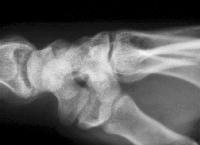

The scapholunate angle is abnormal, about 80 degrees.

Radial and ulnar deviation views show minimal additional scapholunate widening in ulnar deviation.